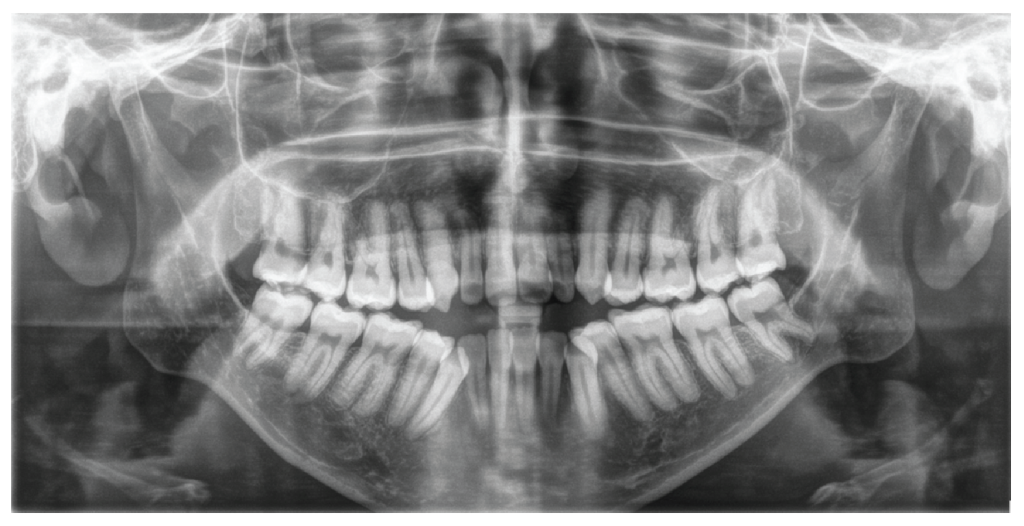

Figure 3: Panoramic radiography of a patient with Nemaline Myopathy. Initial panoramic radiograph shows all teeth fully developed, the absence of 4 premolars, rounded dental roots, long and narrow condylar neck, short coronoide process, marked antegonial notch. All teeth were fully developed. The mesial inclination of the maxillary and mandibular posterior teeth was prominent, typical of anterior open bite cases.